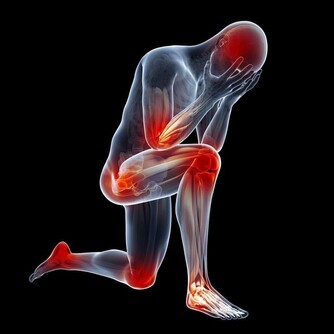

“腎虛”是很多人比較敏感的詞語,尤其是男性朋友。腎虛屬於一種中醫名詞,是指腎臟的精氣不足,主要症狀有四肢乏力、腰膝酸軟、盜汗、畏寒等等。腎虛不僅有損身體健康,同時也會降低生活品質。我們先來看一看百度百度怎麼解釋腎虛的:

腎虛指腎臟精氣陰陽不足。腎虛的種類有很多,其中最常見的是腎陰虛,腎陽虛。

腎虛的症狀:腎陽虛的症狀為腰酸、四肢發冷、畏寒,甚至還有水腫,為“寒”的症狀,性功能不好也會導致腎陽虛;

腎陰虛的症狀為“熱”,主要有腰酸、燥熱、盜汗、虛汗、頭暈、耳鳴等。現代科學證明,當人發生腎虛時,無論腎陰虛還是腎陽虛,都會導致人的免疫能力的降低,有更多的證據表明,腎虛發生時,腎臟的免疫能力降低,而腎臟的微循環系統亦會發生阻塞,腎絡呈現不通。所以對於腎虛的治療應防治結合。